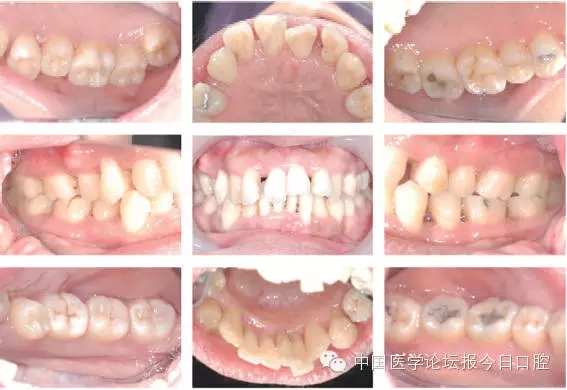

图1为患者初诊的口内相,图2为我们为患者进行检查的牙周记录表,图3为患者的全口根尖X线片,从中我们可以发现几个关键问题:

患者全口牙列不齐,前牙深覆牙合,21唇侧移位,11与12间、21与22间有2mm间隙,14、13与44对刃。

▲图1 患者初诊口内相,黑圈处为牙龈明显水肿或溢脓部位,蓝圈处为14、13与44对刃咬合部位